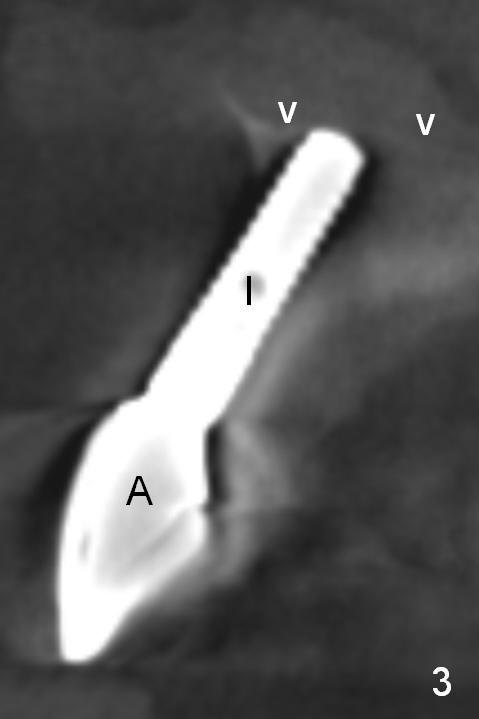

The implant at the site of #8, which was placed ~ 2 years ago, appears devoid of bone buccally (Fig.1 (CBCT 3 D image) I). Fig.2,3 are coronal sections of the tooth #9 (B: buccal) and 8 (A: Zirconium abutment), respectively. Fig.4 is a coronal section of the tooth #5 post-immediate implant with the bone plate (>, different case). With placement of a 15° Titanium abutment (Fig.5 palatal green line), the crown profile may improve.